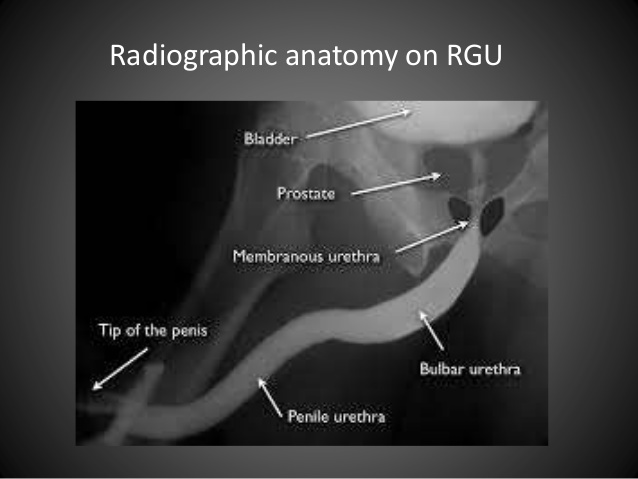

Quando está contraindicada a sondagem vesical para avaliar a reposição volêmica? O que fazer nesses casos?

Sangue no meato uretral, retenção urinária, hematoma perineal, suspeita de fratura de pelve

Antes de sondar, afastar lesão de uretra com uretrocistografia retrograda

,Lesão de qual tipo de uretra…

- Queda a cavaleiro

- Ferimento penetrante, ataque de animais

- Fratura, luxação de bacia

ANTERIOR

Lesão de uretra bulbar: Queda a cavaleiro

Lesão de uretra peniana: Ferimento penetrante, ataque de animais

POSTERIOR

Lesão de uretra memebranosa: Fratura, luxação de bacia